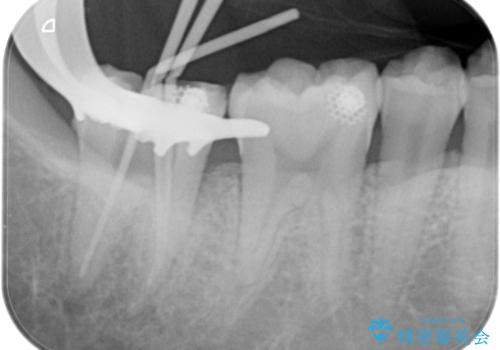

【根管治療】ズキズキ痛い歯の治療

- 奥歯がズキズキ痛いことを主訴に来院されました。

不可逆性歯髄炎の診断により根管治療を行なっております。

根管治療を行なった歯は速やかに歯冠修復が必要です。